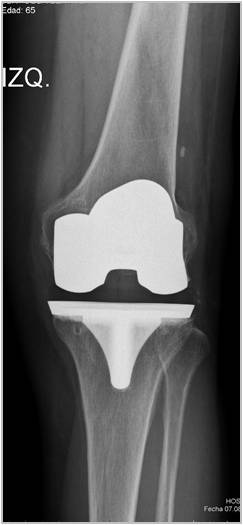

Introducción: El objetivo de este trabajo fue analizar los resultados funcionales y el rango de movimiento entre tres grupos de pacientes con artroplastia total de rodilla: dos utilizando prótesis de alta flexión y el otro con un diseño convencional. Materiales y Métodos: 64 pacientes fueron operados con prótesis total de rodilla Zimmer NexGen®, y 34 pacientes operados con Optetrack ® de alta flexión. Luego de la exclusión de pacientes; 22 pacientes (grupo A) fueron tratados con diseño de alta flexión de Zimmer, 21 pacientes (grupo B) tratados con prótesis Zimmer convencional, y 25 pacientes (Grupo C) con artroplastia Optetrack® PS. La evaluación funcional se realizó con el Knee Society Score, el Western Ontario and McMaster Universities osteoathritis index y la escala analógica visual. Resultados: En el posoperatorio, el promedio de flexión máxima del grupo A subió de 99° a 113º, con un aumento promedio de 14º, en el grupo B de 106° a 118º con una ganancia promedio de 12º y en el grupo C de 110° a 111° siendo la ganancia de 1°. Los resultados funcionales evaluados con KSS y el WOMAC presentaron mejorías en los tres grupos. Conclusión: Las evaluaciones clínicas funcionales son favorables en los tres diseños evaluados. Este estudio muestra que no hay diferencias significativas en la flexión final lograda, y resultados funcionales entre los dos primeros diseños entre sí, si siendo estos significativamente superiores al diseño del tercer grupo luego de un año de seguimiento. Palabras Claves: Prótesis total de rodilla, prótesis de alta flexión, prótesis convencionales, rango de movilidadDescargas